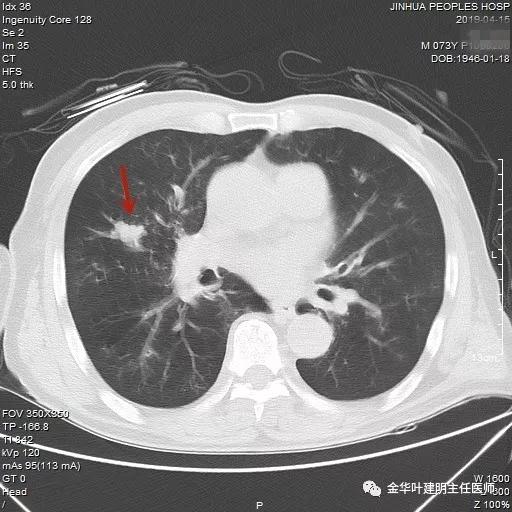

吴某不同意肺穿刺,咳嗽咳痰好转后就出院了。此后于今年6月份回院复查,仍然住在内科,这次想通了,同意肺穿刺,结果病理果然是肺癌,是低分化鳞癌。因为吴某与本院一院级领导是同村的,便让我去会诊。我觉得虽然从病灶来看可以手术,纵隔内也无明显转移的肿大淋巴结,相关检查也无远处转移证据。但患者年纪较大,平时有慢支与肺气肿,发作时还有喘憋症状,肺功能也示重度混合型通气功能障碍,MVV重度下降。询问吴某,平时一口气走上3楼是有困难的,所以行右肺上叶切除术后出现呼吸功能不全的概率还是比较高的,手术存在较大风险。争取手术也是为争取根治以至得到较长期生存的机会。若同意手术,也要家属与患者都十分理解,并对术后需要呼吸机辅助以及无法脱离呼吸机支持都有充分的思想准备。而若放弃手术,则主要是免疫治疗及放化疗,其中放化疗对肺功能也有一定影响,且无法达到根治的目的。我当时告诉吴某儿子,要开,做好术后出现呼吸功能衰竭的准备,且不能责怪我的同事和我本人;若暂不手术,也可回当地考虑保守治疗;当然也可先戒烟、锻炼肺功能、使用支气管扩张剂等改善肺功能,较短时间内再回院复查肺功能,再争取手术。吴某当时办理了出院手续,也没有与我们确认是否考虑手术。下面是当时6月份时候的片子以及肺穿刺情况:

绿色箭头示穿刺针,红色箭头示肿瘤